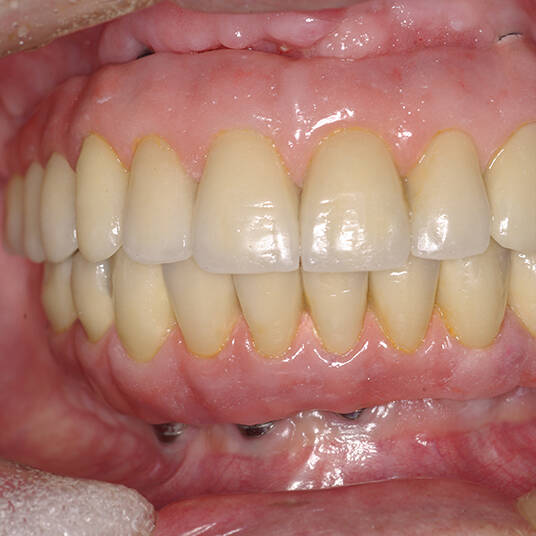

Na Clínica Pontes Odontologia, somos referência em implantes dentários em Fortaleza, oferecendo tratamentos de alta qualidade e tecnologia de ponta. Os implantes dentários são estruturas de titânio posicionadas cirurgicamente no osso maxilar ou mandibular para substituir as raízes dos dentes ausentes. Essa técnica permite a fixação de próteses personalizadas, restaurando a função mastigatória, a estética e a autoestima dos nossos pacientes.

Utilizamos a tecnologia CAD CAM, um sistema avançado que possibilita a confecção precisa das próteses dentárias diretamente sobre os implantes. Esse método inovador garante um ajuste perfeito, um resultado estético superior e proporciona muito mais conforto e durabilidade. Com o CAD CAM, nossos pacientes contam com um processo mais rápido e previsível para alcançar o sorriso desejado.